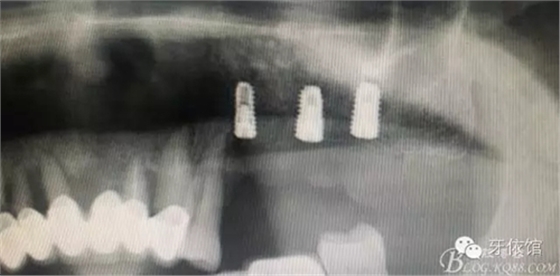

患者男性,62歲,X光片顯示竇底有二維20x15mm囊腫,竇膜內(nèi)無內(nèi)容物

計劃:1.外開窗2.摘除囊腫3.植骨期植入植體

植骨量1.5g